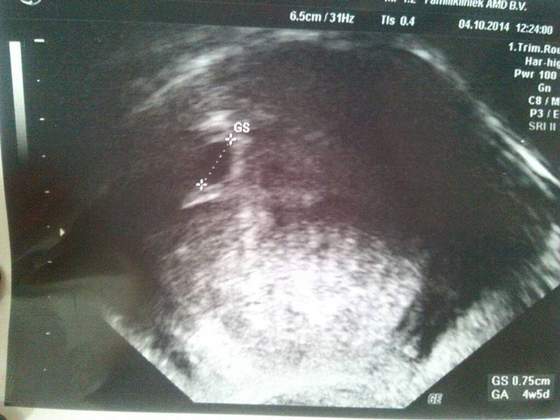

Malgos bylam u gina. Dala mi duphaston i mam lezec. Fasolka mniejsza niz powinna byc bo ma 0.75cm i wychodzi 4w5d a z moich obliczen wychodzi 5w4d a z OM jeszcze lepiej bo 8w :-\